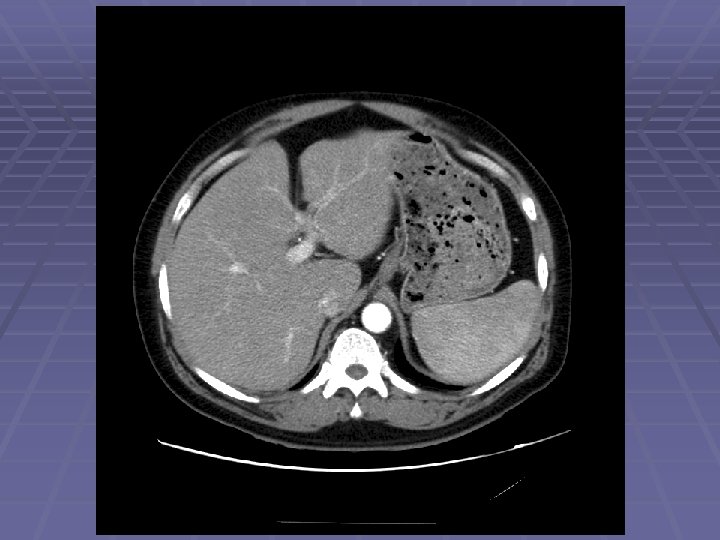

EUS Evaluation of Left Lobe of Liver